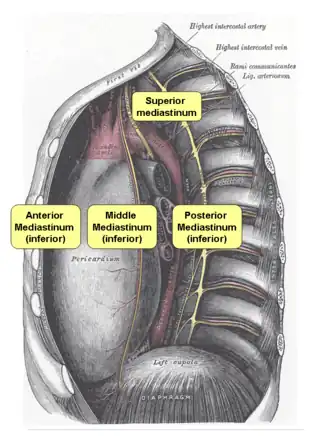

Acute mediastinitis is an infectious process and can cause fever, chills, and tachycardia. Pain can occur with mediastinitis but the location of the pain depends on which part of the mediastinum is involved. When the upper mediastinum is involved, the pain is typically retro-sternal pain. When the lower mediastinum is involved, pain can be located between in the scapulae and radiate around to the chest.[2]

With regards to CT Imaging, the extent of involvement of the mediastinum can be evaluated. Therefore, acute mediastinitis can be classified into three categories:[9]

- diffuse mediastinitis

- isolated mediastinal abscess

- mediastinitis or mediastinal abscess complicated by empyema or subphrenic abscess.